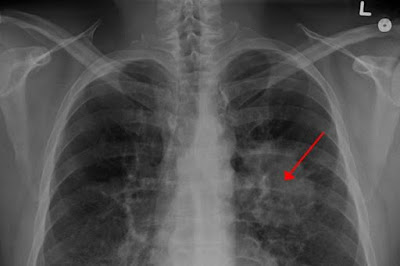

Ο μη-μικροκυτταρικός καρκίνος πνεύμονα (ΜΜΚΠ) είναι μία μορφή καρκίνου του πνεύμονα. Παρατηρείται όταν τα φυσιολογικά κύτταρα του πνεύμονα μετατρέπονται σε παθολογικά και πολλαπλασιάζονται αυτόνομα και ανεξέλεγκτα. Ο μη-μικροκυτταρικός καρκίνος του πνεύμονα αναπτύσσεται πιο αργά και τον συναντάμε πιο συχνά. Διακρίνεται σε τέσσερα στάδια, στα οποία κατατάσσεται η εξέλιξή του ανά περίπτωση, ανάλογα με το πόσο έχει εξαπλωθεί.

Ο ΜΜΚΠ είναι ο πιο συχνός τύπος καρκίνου του πνεύμονα που αντιπροσωπεύει το 85-90% όλων των περιστατικών. Από αυτά, το 2-7% άγονται από την αναδιάταξη του γονιδίου ALK (κινάση αναπλαστικού λεμφώματος) – ενός γονιδίου το οποίο μπορεί να συντηχθεί με άλλα γονίδια για να δημιουργήσει μία μη φυσιολογική «πρωτεΐνη σύντηξης», που προάγει την δημιουργία και ανάπτυξη ορισμένων όγκων σε μορφές καρκίνου όπως ο μη-μικροκυτταρικός καρκίνος του πνεύμονα.